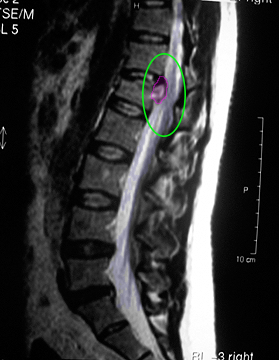

Κήλη θωρακικού μεσοσπονδύλιου δίσκου με πίεση στην τελική μοίρα του νωτιαίου μυελoύ